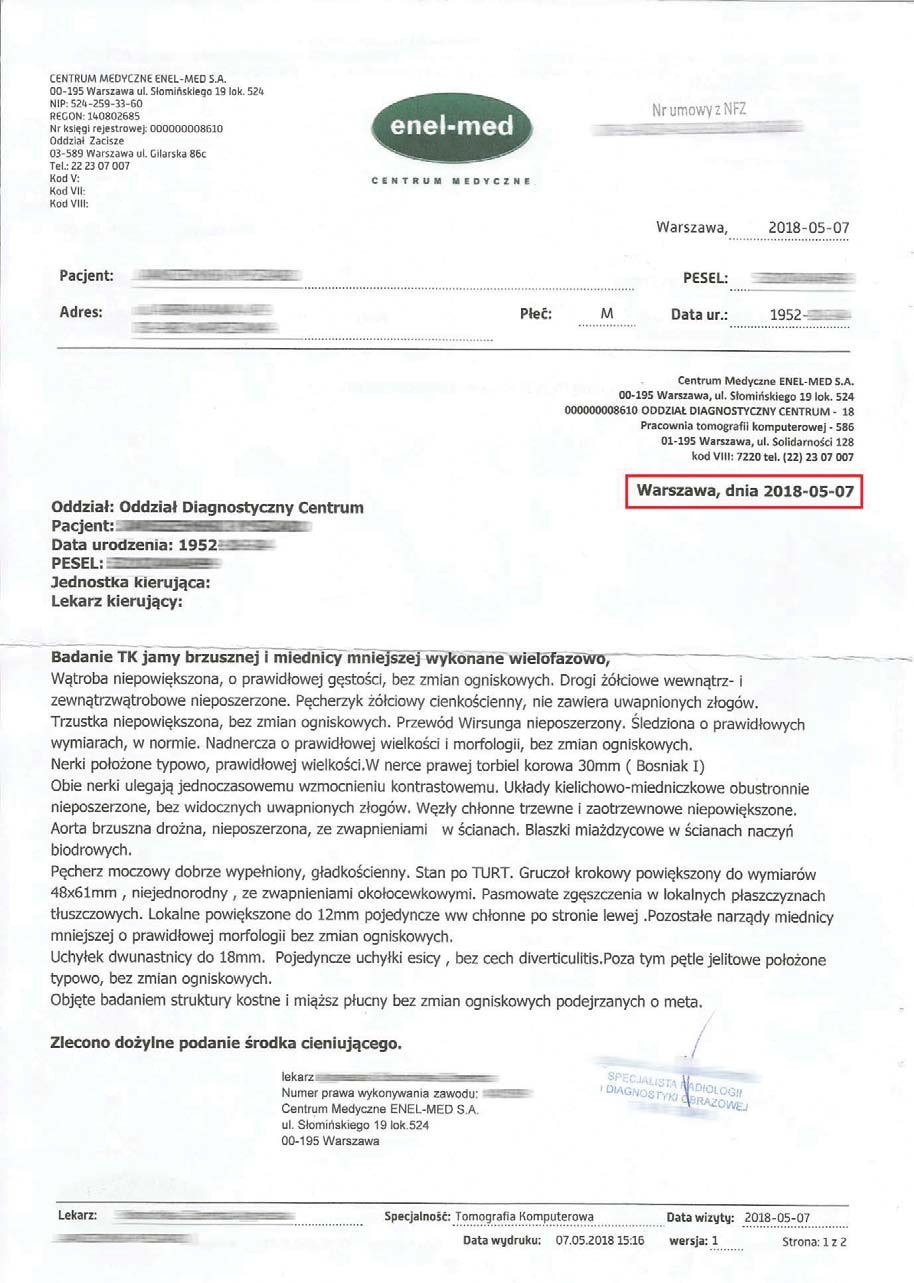

EFEKT PREPARATU NA GUZIE HYPOECHOGENNYM

Mężczyzna lat 66 z guzem hypoechogennym o wymiarach początkowych 16x10mm i wymiarach prostaty 55x47 mm zastosował terapię preparatem, a po 3 miesiącach zaobserwowano pierwsze zmiany w postaci zmniejszenia ogniska do wymiarów 6x7 mm a także zmniejszenie rozmiarów samej prostaty do 50x40 mm.

Badanie po 6 miesiącach stosowania preparatu wykazało brak guza- potwierdzone badaniem obrazowym, dodatkowo prostata zmniejszona do rozmiaru optymalnego (48x61mm), charakterystycznego dla grupy wiekowej. Pełny zanik guza w tak krótkim czasie bez ingerencji chemio i radioterapii wskazuje na głęboką regenerację komórkową. Preparat stymulując mitochondria dostarcza zwiększoną ilość mitochondrialnego ATP, dzięki któremu dochodzi do apoptozy uszkodzonych komórek prostaty. Proces regeneracji komórkowej poprzez stymulację i zabezpieczenie struktury i funkcji mitochondriów wycofuje niekontrolowany podział, co wskazuje na działanie antynowotworowe bez toksyczności.